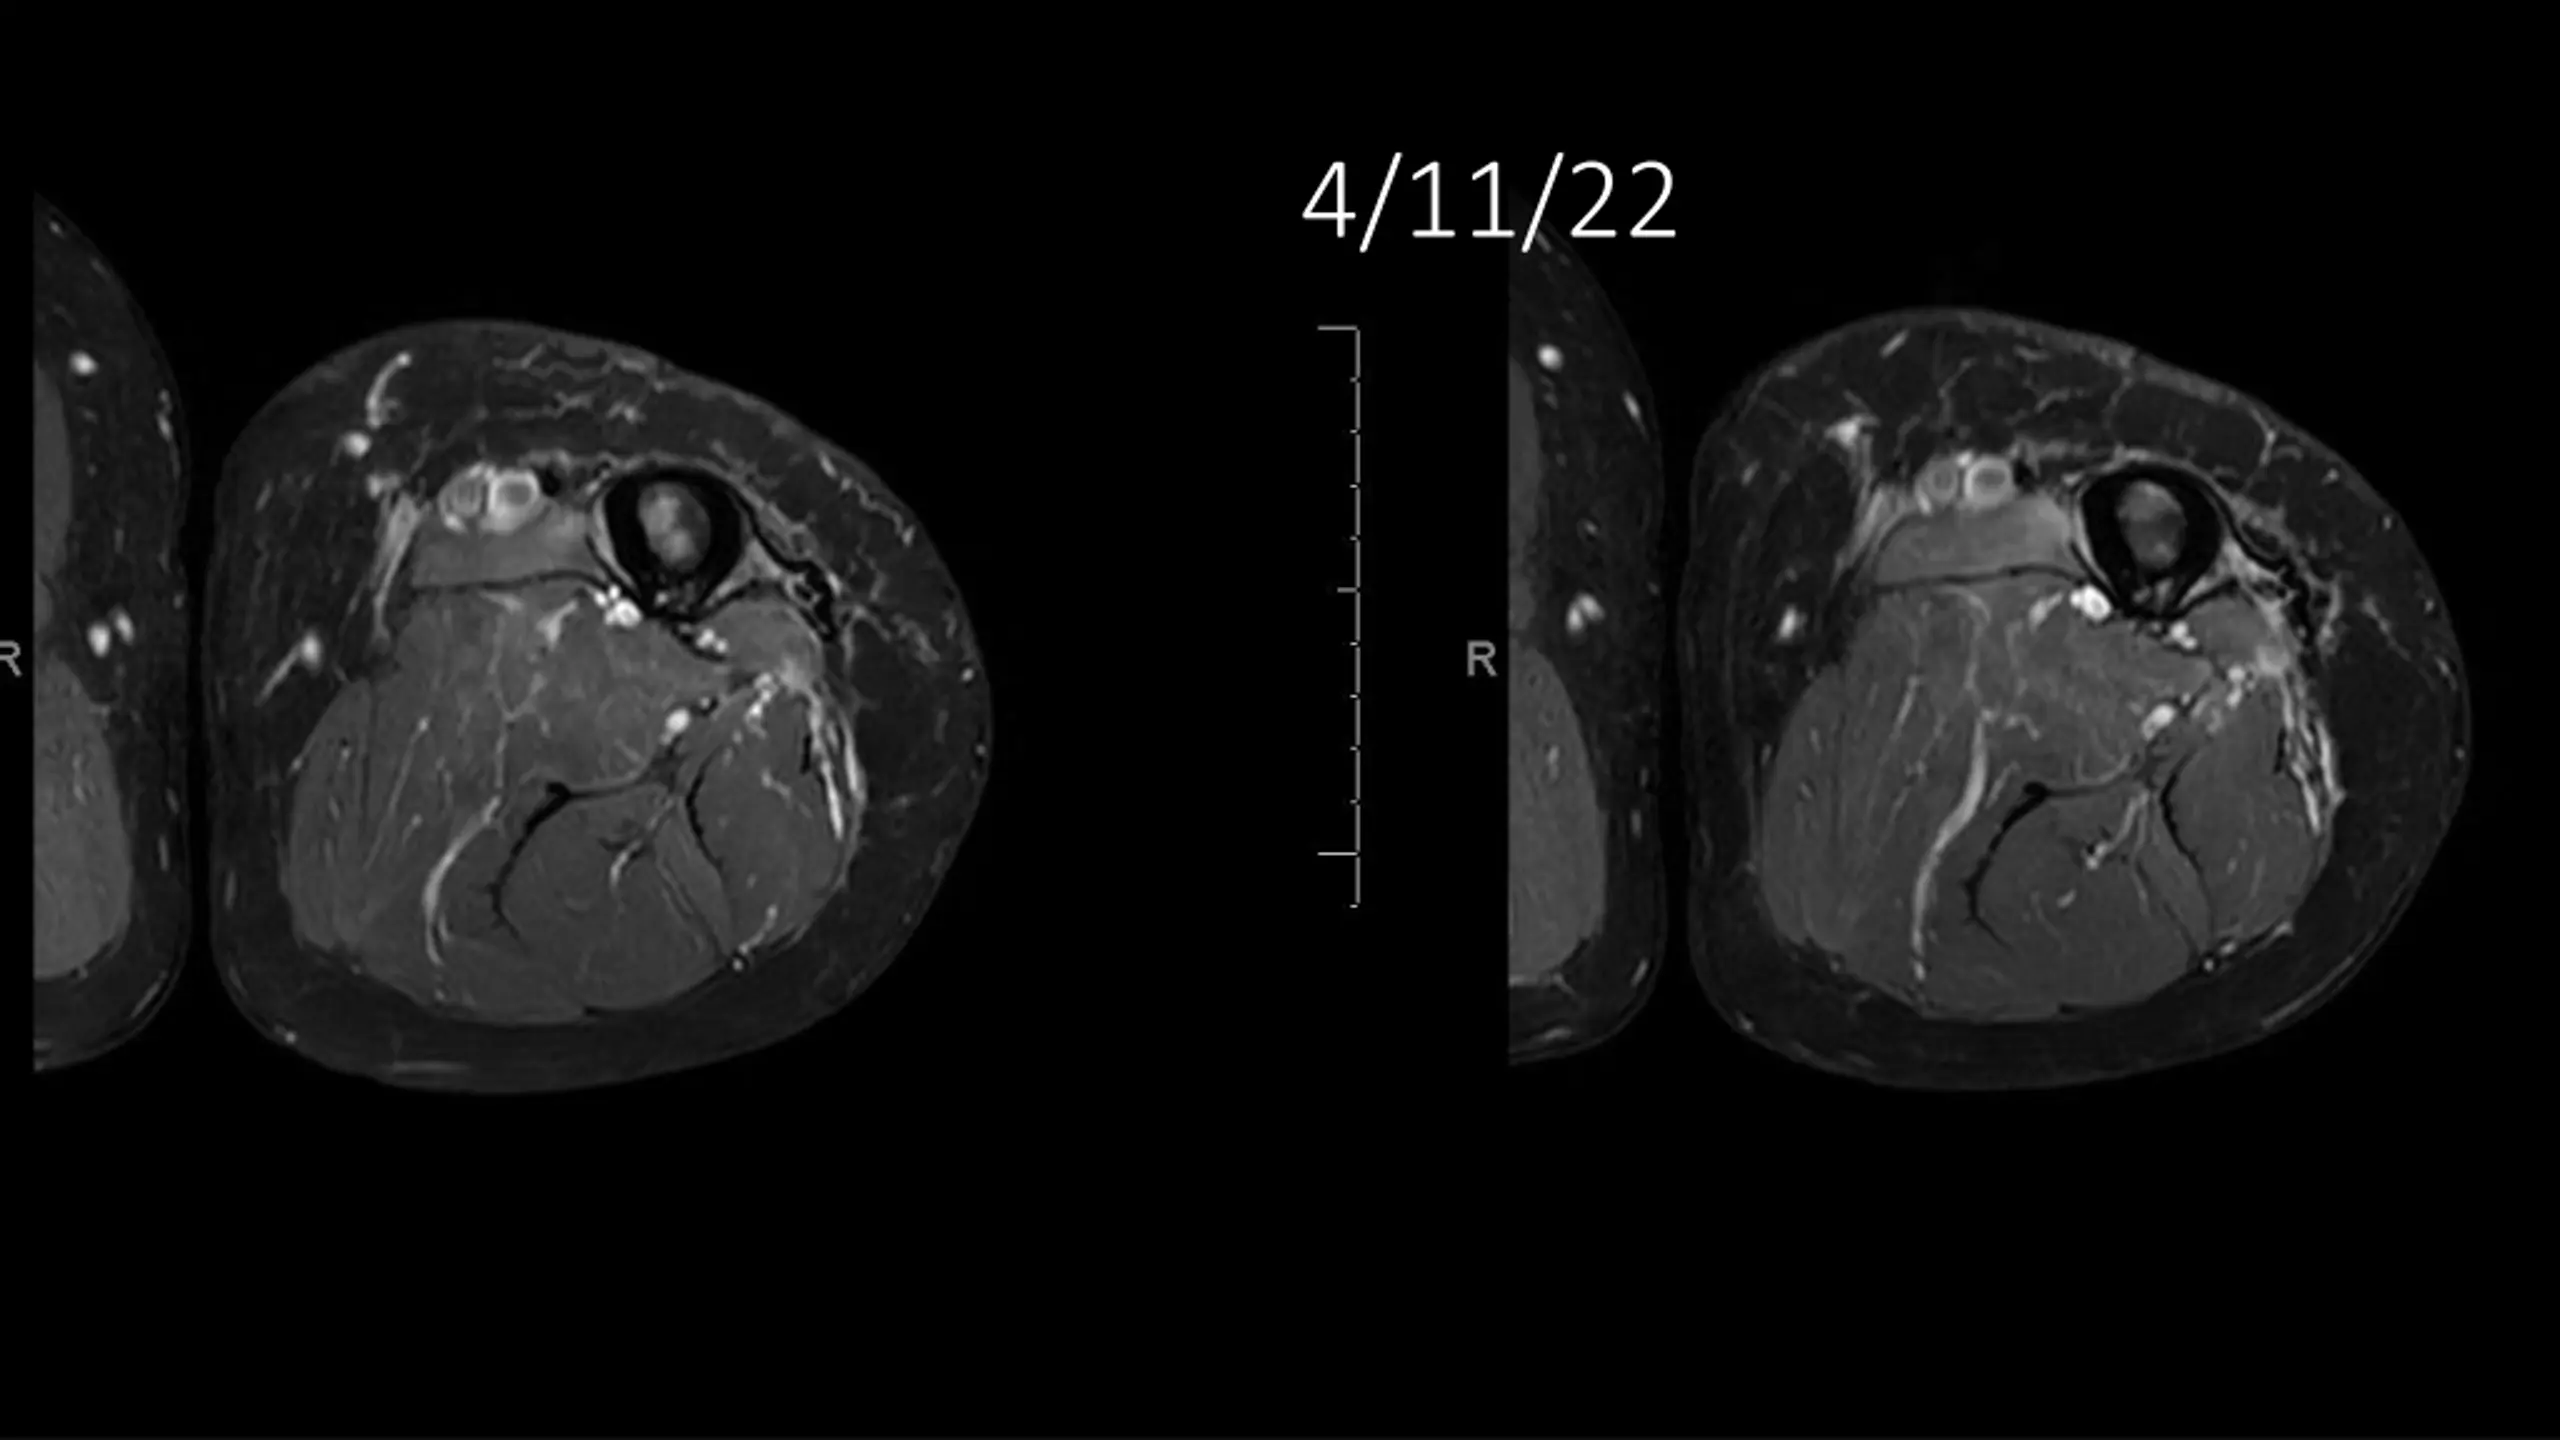

62-year-old shows post-surgery progress from 11/4/2020 to 4/11/22

Explore the journey of a 62-year-old individual post-UPS resection on 11/4/2020, through a series of dated images leading up to 4/11/22. Witness the transformation and recovery process in these visual updates reflecting the progression over time.